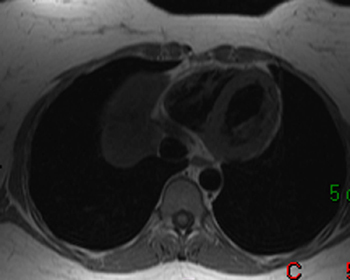

16) What aortic abnormality is seen on the T1 weighted axial image below?